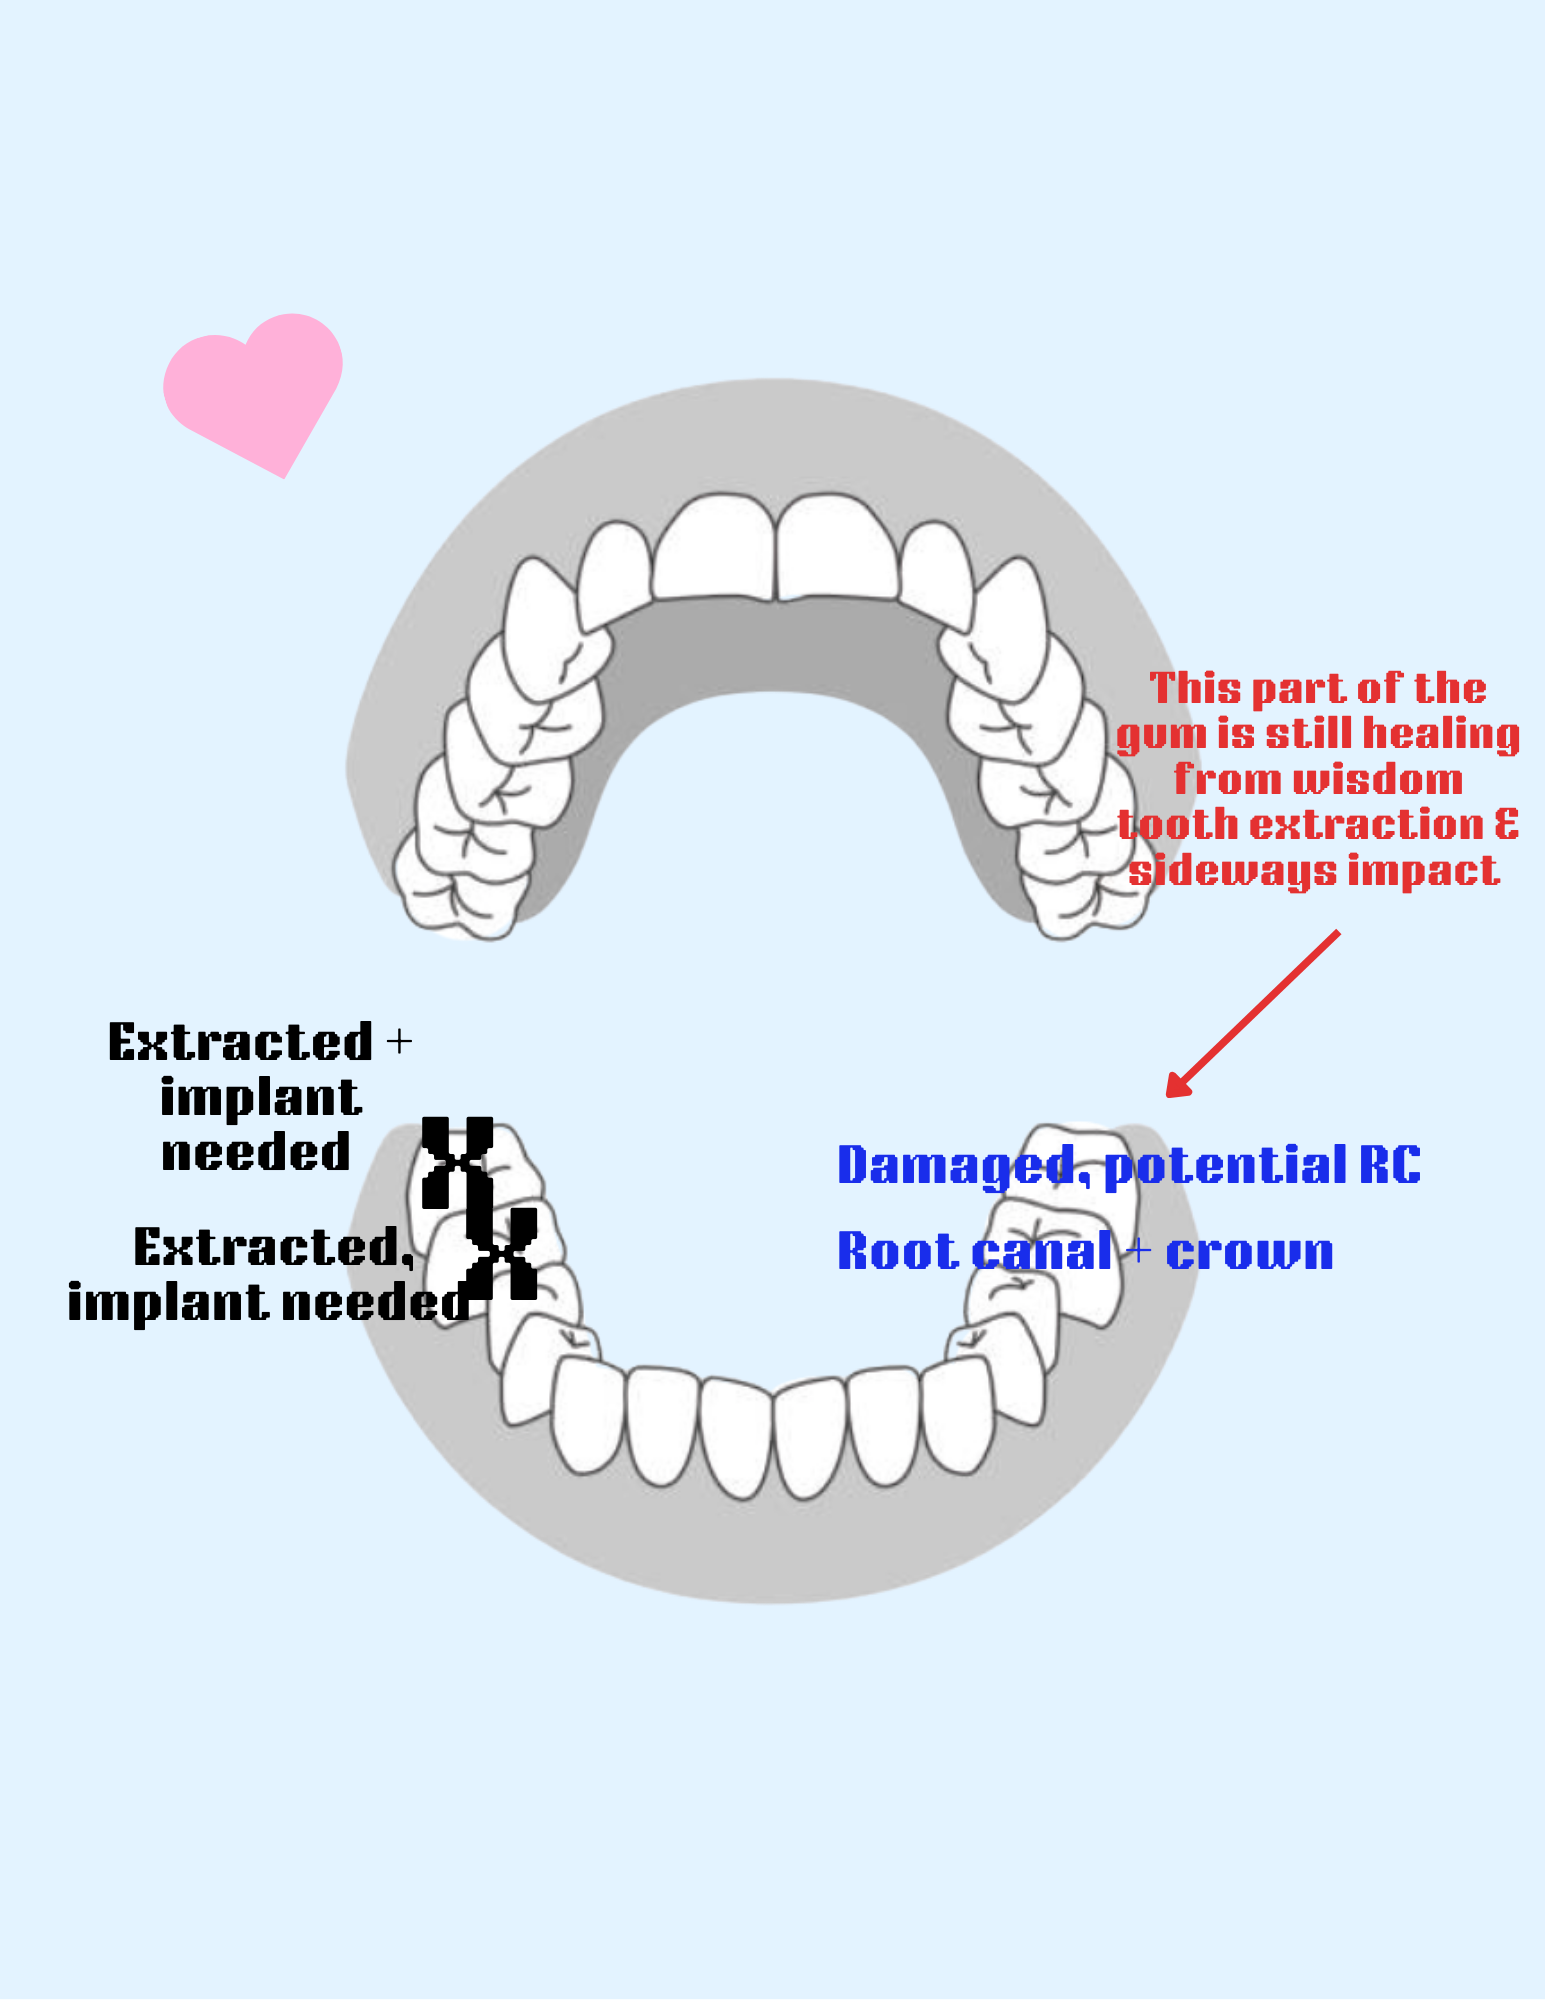

So far, I have had 5 teeth extracted, 3 were wisdom teeth which needed to come out, but 2 were main molars on my right bottom side that dentists could not save because they were too damaged by wisdom teeth that came in. I need these to chew and have a fully operating mouth. If I do not get implants I risk losing my top teeth because they can shift or super-erupt. I also risk bone loss or disfigurement to my jaw. Worst of all, I won't be able to eat or speak properly. I’m young, so a denture is not advised. Right now I’m pretty gummy on that bottom right side and lisping a little bit lol.

On top of this, I had an emergency root canal on my left side that is in need of a crown and before I can get a crown on that tooth I need surgery to shave down the bone. The molar next to that one, the one impacted by the wisdom tooth directly, is going to be sensitive for a while due to bone resorption.

I made a diagram to explain what’s going on.